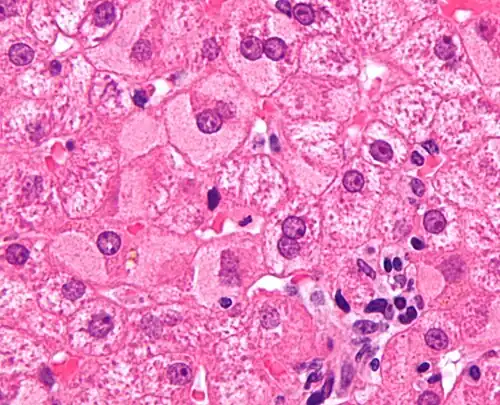

| Micrograph showing ground glass hepatocytes, which are seen in chronic hepatitis B infections (a type of viral hepatitis), and represent accumulations of viral antigen in the endoplasmic reticulum. H&E stain. | |